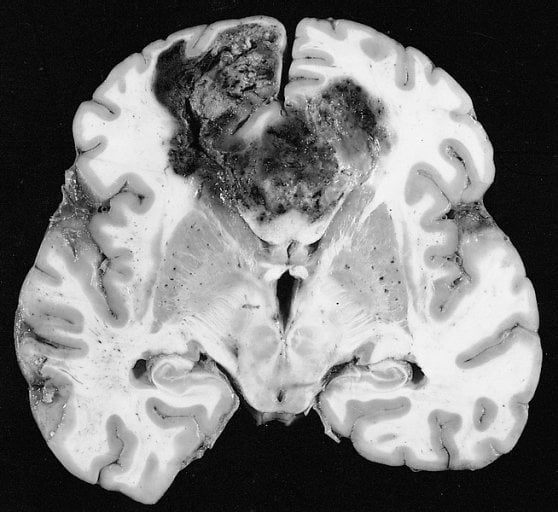

Glioblastoma multiforme is the most common and aggressive form of brain cancer, with a median survival of about 15 months. A major obstacle to improving treatment for the 3,470 cases of the disease expected in the United States this year is the blood-brain barrier, the name given to the tight fit of cells that make up the blood vessels in the brain. That barrier protects the brain from toxins in the blood but also keeps drugs in the bloodstream from reaching brain tumors.

Image Source: The glioblastoma multiform brain slice image is credited to Dr. Rodney D. McComb and is in the public domain.